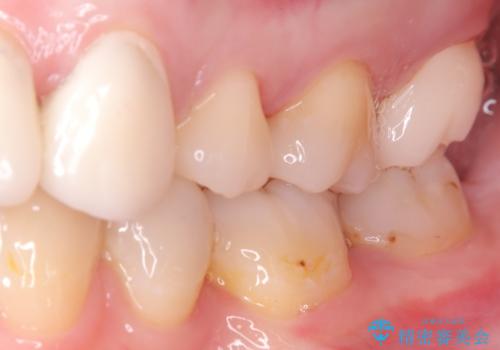

奥歯に虫歯があると言われた セラミッククラウンでキレイで長持ちする歯へ

担当医 榊原康平